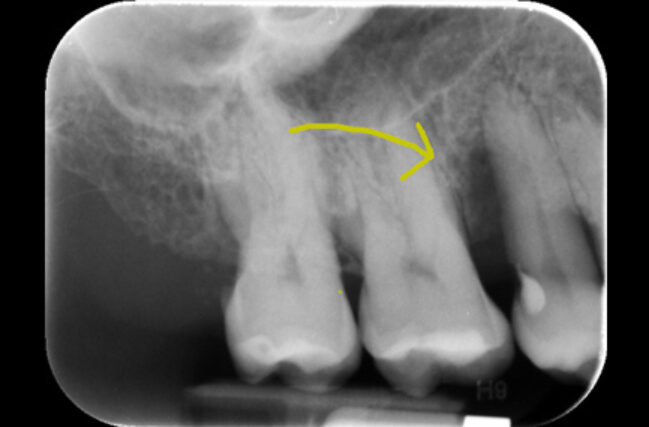

Periodontal surgery provides improved access to the roots and bone hidden under the inflamed gum. The gum is carefully peeled back to allow thorough decontamination of the root surface. Depending on the pattern of bone loss, a decision may be taken to re-contour the bone; which would allow the gum to heal in a more predictable manner.

In certain situations, there may be an opportunity to regenerate the lost bone. Bone grafting materials and special tissue stimulating proteins can be used to aid the re-growth of natural bone and improve the overall support for the tooth.